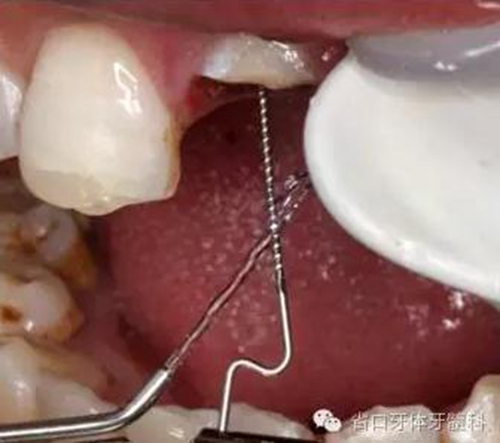

圖9. 腭側(cè)電刀切齦止血、暴露斷面,殘根斷面磷酸酸蝕

圖12. 超聲蕩洗纖維樁道